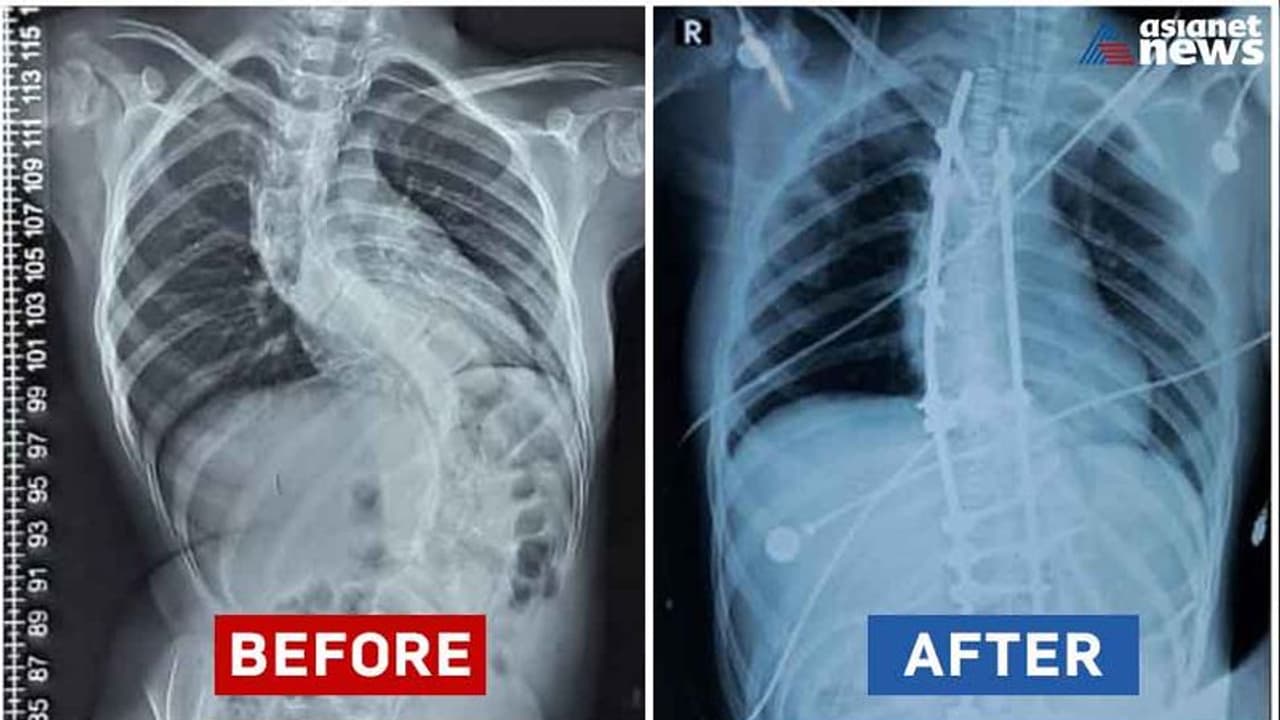

തിരുവനന്തപുരം: നവകേരള സദസ് തിരുവനന്തപുരത്ത് അവസാനിക്കുമ്പോള് കുഞ്ഞു ഫാത്തിമക്ക് നിവര്ന്ന് നടക്കാമെന്നുള്ള സന്തോഷം പങ്കുവെച്ച് ആരോഗ്യ മന്ത്രി വീണ ജോര്ജ്. ഫാത്തിമക്ക് ജന്മനായുള്ള രോഗാവസ്ഥയായിരുന്നു എപിഫൈസിയല് ഡിസ്പ്ലേസിയ (epiphyseal Dysplasia). അതുമൂലം ഫാത്തിമയുടെ നട്ടെല്ലിന്റെ വളവ് ക്രമാതീതമായി ഉയരുന്ന സ്കോളിയോസിസ് (Scoliosis) എന്ന അസുഖം ഉണ്ടായിരുന്നു. ഇക്കാരണം കൊണ്ട് ശ്വാസകോശ സംബന്ധമായതും നാഡീ സംബന്ധമായതുമായ വൈകല്യങ്ങള് ഉണ്ടാവാനുമുള്ള സാധ്യതയുമുണ്ടായിരുന്നു.

ഇത് സാധാരണ കുട്ടികളില് കാണുന്ന adolescent idiopathic scoliosisന്റെ ചികിത്സയേക്കാള് ബുദ്ധിമുട്ടുള്ളതും സങ്കീര്ണതകള് നിറഞ്ഞതുമാണ്. ശസ്ത്രക്രിയക്ക് ശേഷം കുഞ്ഞു ഫാത്തിമ സുഖം പ്രാപിച്ചു വരുന്നു. ഡോ. ബി എസ് സുനില് കുമാറിന്റെ നേതൃത്വത്തില് ഡോ. ജിതിന്, ഡോ. ജിയോ, ഡോ. കൃഷ്ണകുമാര്, ഡോ. അനന്തു എന്നീ ന്യൂറോ സര്ജറി വിഭാഗം ഡോക്ടര്മാരും, അനസ്തേഷ്യ വിഭാഗത്തിലെ ഡോ ബാബുരാജിന്റെ നേതൃത്വത്തില് ഡോ. ബിന്ദു, ഡോ. സുനില് കുമാര്, ഡോ. സെലീന, ഡോ. അഞ്ജു എന്നിവരും, സ്റ്റാഫ് നേഴ്സുമാരായ സരിത, ദീപ്തി എന്നിവരും ശസ്ത്രക്രിയയില് പങ്കാളികളായി. ഓപ്പറേഷന് മുമ്പും ശേഷവുമുള്ള കുഞ്ഞ് ഫാത്തിമയുടെ എക്സ്റേ ചിത്രവും മന്ത്രി ഫേസ്ബുക്കിൽ പങ്കുവച്ചിട്ടുണ്ട്.